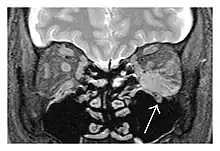

The extent of inflammation that can occur in IgG4-ROD is well demonstrated on magnetic resonance imaging (MRI).

Infraorbital nerve enlargement (IONE) is considered to be a particularly suspicious sign of IgG4-ROD, but seems to occur only when inflammation is in direct contact with the infraorbital canal.[10] IONE is defined as the infraorbital nerve diameter being greater than the optic nerve diameter in the coronal plane.

![]() Enlargements in the left inferior rectus muscle and infraorbital nerve (arrow) in a 65-year-old man with a serum IgG4 of 404 mg/dL.[1] (T2-weighted MRI) |